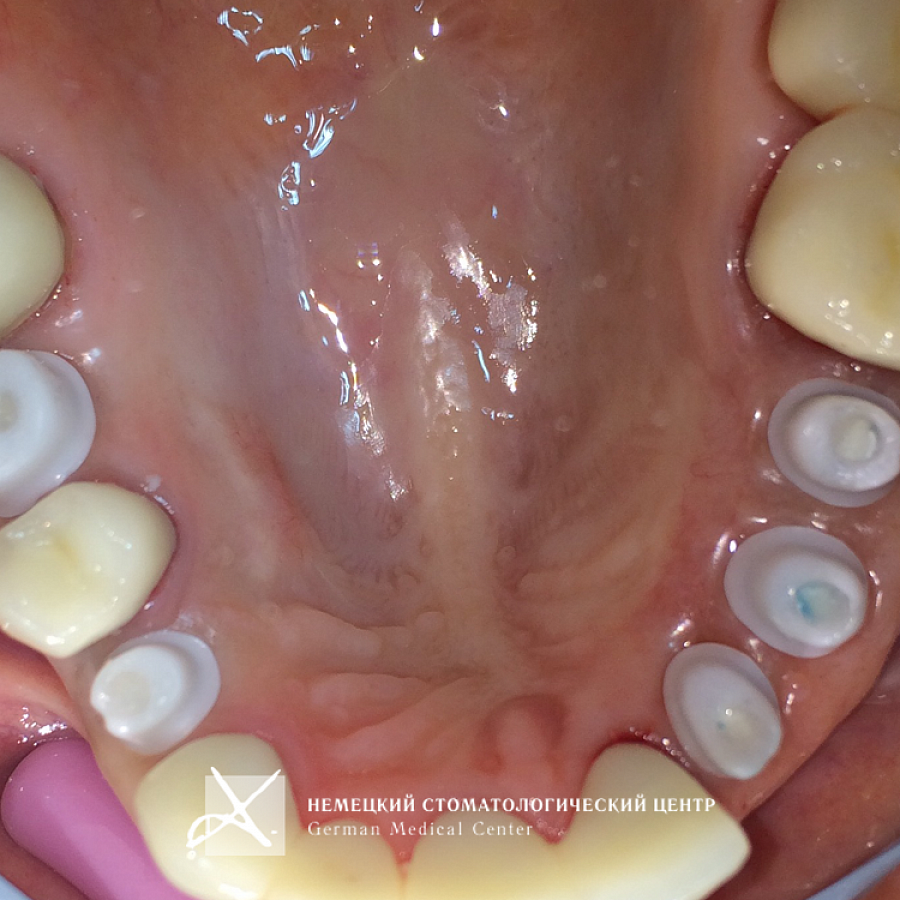

Пациентка обратилась с задачей восстановить целостность зубных рядов.

Пациентке проведено полноценное восстановление зубных рядов конструкциями с опорой на зубы и имплантаты. Коронки и абатменты изготовлены из диоксида циркония. Во время подготовительных мероприятий пациентка пользовалась временными конструкциями.